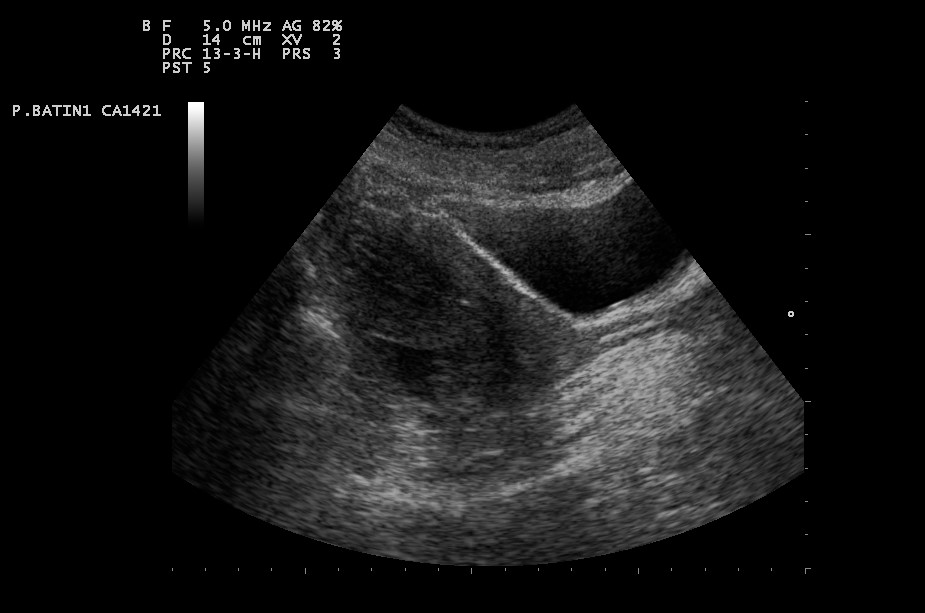

Douglas boşluğunda sıvı birikmesi durumu genellikle kadın doğum hekimine başvuran hastaların ultrason yöntemi ile muayenesi esnasında tespit edilmektedir. Bu alanda biriken sıvı elle yapılan fizik muayenelerde kolayca tespit edilemez.

Genelde ultrason yöntemiyle tespit edilse de BT gibi ileri görüntüleme tetkiklerinde de bu sıvı görülebilmektedir. Douglasta sıvı artışı yeteri kadar olduğunda ultrasonda rahatlıkla teşhis edilir.